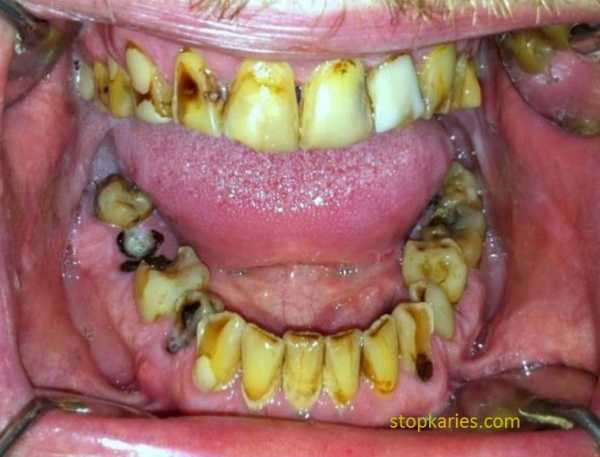

- И на последок, небольшой клинический случай. К стоматологу могут прийти с этим.

У данного пациента множественный кариес, пародонтит, переодонтит нескольких зубов, хронические пульпиты, патология прикуса, повышенная стираемость зубов, клиновидные дефекты. Не правильно расположенные нижние зубы мудрости.

Данная ситуация — довольно распространенный в практике случай.